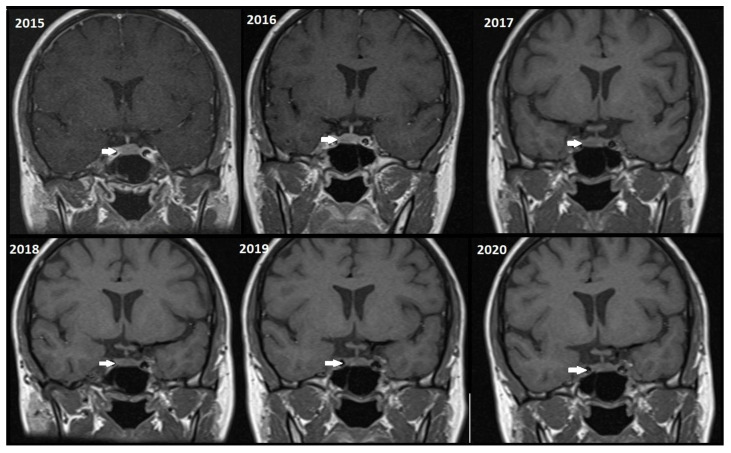

简介和目的:动态对比增强磁共振成像(DCE-MRI)已被用作诊断和跟踪垂体微腺瘤的金标准。然而,钆基造影剂(gbca)的使用存在长期滞留组织和不良反应的潜在风险。本研究旨在评估非对比MRI (T1W和T2W序列)在垂体微腺瘤随访成像中的敏感性,并试图与DCE-MRI进行比较,评估肿瘤随时间的稳定性。材料和方法:我们回顾性分析了2020年至2024年间300例垂体MRI扫描。纳入确诊的微腺瘤(≤10 mm)患者。非对比(T1W/T2W)和DCE-MRI序列由经验丰富的放射科医生对任何临床信息进行分析。评估检出率和肿瘤大小的变化。结果:79例微腺瘤T1W检出率为55.7%,T2W检出率为70.9%,DCE-MRI检出率为88.6%。随访期间未见明显肿瘤生长(平均大小4.80±2.3 mm vs. 4.81±2.4 mm, p < 0.05)。结论:虽然对早期诊断更为敏感,但非对比MRI能够显示大多数检测到的微腺瘤,并排除明显生长的病例,因此支持在稳定病例的随访影像学中省略钆。这可能转化为更低的成本和降低患者的风险,从对比相关的危害。

Introduction and objectives: Dynamic contrast-enhanced magnetic resonance imaging (DCE-MRI) has been used as a gold standard in diagnosing and following pituitary microadenomas. However, the use of gadolinium-based contrast agents (GBCAs) involves a potential risk of long-term retention in tissues and adverse reactions. This study aimed to evaluate the sensitivity of non-contrast MRI (T1W and T2W sequences) in follow-up imaging of pituitary microadenomas, attempting a comparison with DCE-MRI, assessing tumor stability over time.

Materials and methods: We retrospectively reviewed 300 pituitary MRI scans between 2020 and 2024. Included were patients with confirmed microadenomas (≤10 mm). Non-contrast (T1W/T2W) and DCE-MRI sequences were analyzed by an experienced radiologist blinded to any clinical information. Detection rates and changes in tumor size were evaluated.

Results: Detection rates for 79 microadenomas were 55.7% for T1W, 70.9% for T2W, and 88.6% for DCE-MRI. There was no significant tumor growth during the follow-up (mean size 4.80 ± 2.3 mm vs. 4.81 ± 2.4 mm, p > 0.5).

Conclusions: While still more sensitive for the primary diagnosis, the non-contrast MRI was able to visualize the majority of detected microadenomas, and significant growth was ruled out, thus supporting the case to omit gadolinium from follow-up imaging in stable cases. This may translate to lower costs and decreased patient risk from contrast-related hazards.